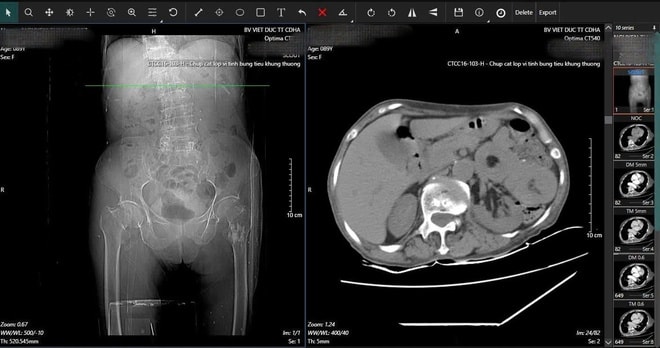

Trong quá trình kiểm tra tổng quát, các bác sĩ BV Hữu nghị Việt Đức phát hiện dấu hiệu bất thường ở vùng bụng. Kết quả chụp CT cho thấy cụ bị lồng ruột do u với khối lồng dài 165mm. Đây là tình trạng cấp cứu nguy hiểm, có thể gây tắc ruột và đe dọa tính mạng nếu không xử lý kịp thời.

Hình ảnh phim X-quang cụ bà 89 tuổi nhập viện gãy cổ xương đùi phải và hình ảnh chụp CT ổ bụng và phát hiện khối u ruột non gây lồng ruột.